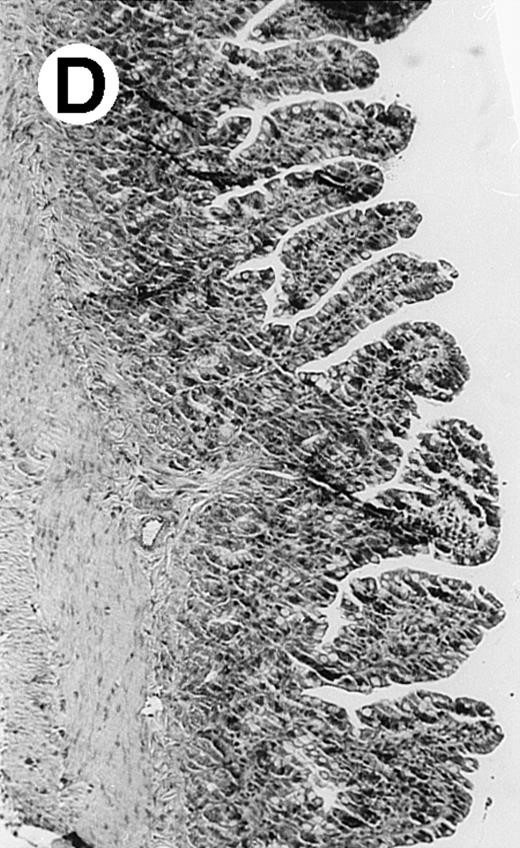

Pathologic findings in the small and large intestine were strikingly different depending on the treatment group. Figure 2A shows a representative pathologic sample from an animal assigned to the control group. Marked thinning of the bowel wall and extensive areas of epithelial cell sloughing was noted. Animals randomized to rhG-CSF treatment had minimal improvement in histologic findings with focal regions of preserved epithelium (Fig2B). Animals randomized to the rhIL-11 group showed substantial improvement with thickening of the epithelial layer and preservation of mucosal cell integrity (Fig 2C). Animals receiving both rhG-CSF and rhIL-11 had the most favorable histologic findings with normal mucosal thickness, minimal inflammatory changes, and preserved tissue architecture (Fig 2D). The composite analysis of the gastrointestinal pathology is provided in Table 1.

Histopathology of small intestinal mucosa cut in transection from an animal in each treatment group (study day 8). The upper panel (row 1) is a low power view (original magnification × 57); the lower panel (row 2) is a high power view (original magnification × 144). Note the diffuse thinning and necrosis of the mucosa with sloughing of intestinal epithelial cells in the control animal (A). There is progressive recovery of the thickness of the mucosa, reduction in inflammatory changes, and improved epithelial architecture with rhG-CSF (B), rhIL-11 (C), and combination therapy with rhG-CSF+IL-11 (D).

rhIL-11 has been shown to have marked effects on gastrointestinal epithelial surfaces. rhIL-11 blocks apoptosis of epithelial cells exposed to radiation and chemotherapy in mice.22 rhIL-11 is protective in a variety of mucositis models and in models of intestinal inflammation.4,23,24 rhIL-11 has been shown to prolong the G-0 phase of growth of intestinal epithelial cells. The precise mechanism of action is not known, but it has been observed that rhIL-11 decreased pRB (retinoblastoma protein) phosphorylation (an important signaling event in cell cycling) within intestinal epithelial cells.32 rhIL-11 has protective effects on gastrointestinal mucosa in transgenic rats, which possess HLA-B27 antigens.4These animals develop an inflammatory colitis that is similar in many respects to human inflammatory bowel disease. rhIL-11 treatment in these animals decreases intestinal inflammation and chronic diarrhea. Based on these preclinical findings, rhIL-11 is currently in clinical trials in both inflammatory bowel disease and chemotherapy-induced mucositis.33 The remarkable capacity of rhIL-11 to protect the gastrointestinal mucosal integrity after chemotherapy is apparent in the current series of experiments (Fig 2).

The beneficial effects of rhIL-11 in the neutropenic rat model may be mediated by its activity as a hematopoietic growth factor, an antiinflammatory cytokine, or its ability to maintain gastrointestinal epithelial integrity.25,33 The results of the current study would favor rhIL-11 protective effects on the intestinal epithelium as the principal mechanism protection in these animals. Maintenance of the gastrointestinal barrier function should diminish the frequency of gut translocation-derived bacterial infection after chemotherapy-induced myelosuppression and epithelial injury.25 The remarkable preservation of membrane integrity found on the gastrointestinal pathologic samples, the reduced circulating levels of endotoxin, and the reduced bacterial load in organ cultures support a dominant role for epithelial protective effects by rhIL-11 treatment in this animal model.